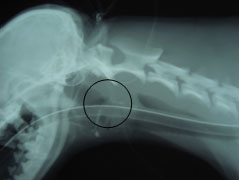

45-01

のどのレントゲン写真。

喉頭にレントゲンに写る異物を認める。